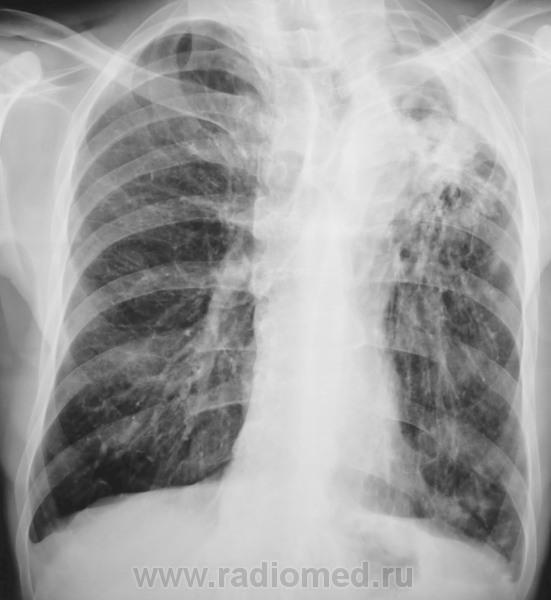

Состояние после торакопластики

Состояние после торакопластики...

Здорово было.Я так понимаю Его Величество, в рецидиве цирротического варианта?